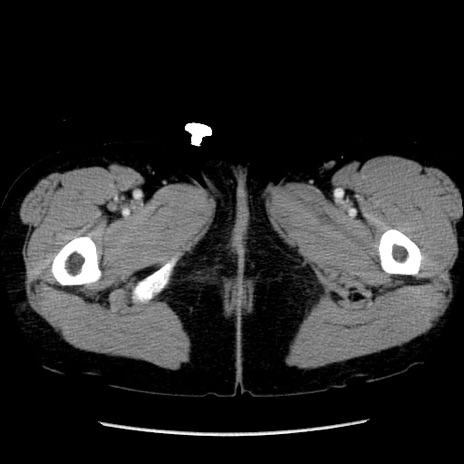

症例6(横断像)

【症例】50歳代女性

【主訴】下腹部痛

【現病歴】本日朝より下痢2回あり。 昼食を食べた後、嘔吐3回、下腹部痛認め、症状軽快せず、当院救急搬送。

最終食事:本日昼(生ものなし)。 昨日の夜、刺身を食ぺたとのこと。周囲に同様の症状の者なし。普段、排便は毎日あるとのこと。

【既往歴】卵巣癌術後(8年前に当院で卵巣摘出)

【身体所見】 意識清明、腹部:平坦、腸蠕動音→、やや硬、下腹部自発痛・圧痛あり、反跳痛あり、筋性防御なし。

【データ】WBC 16000、CRP 0.01